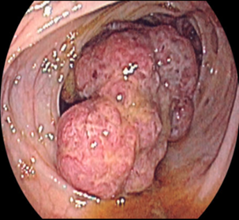

Crohn xəstəliyinin diaqnozu üçün hansı müayinələr vacibdir?

Kolonoskopiya və biopsiya ilə, KT, nəcis analizi

Xoralı kolitin diaqnozu üçün hansı müayinələr vacibdir?

Kolonoskopiya, biopsiya, nəcis analizi